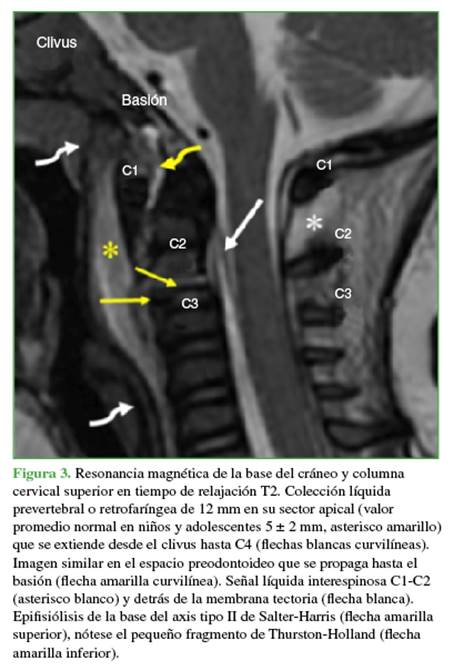

En las radiografías anteroposterior y de perfil, de columna cervical, no se observaron anomalías. El trazado de las cuatro líneas sagitales recomendadas en el trauma era normal. Sin embargo, la relación facetaria C2-C3 era dudosa (Figura 1). La disminución de la entrada de aire en el hemitórax derecho se relacionó con una parálisis diafragmática y atelectasia pulmonar masiva (Figura 2). La RM de columna cervical y base del cráneo reveló una epifisiólisis del axis, una lesión ligamentaria posterior y un importante edema perivertebral (Figura 3).